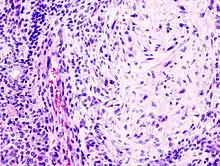

من ناحية نسيجية، فالورم كثير التنوع في مظهره حتى في الأورام الأحادية. نموذجياً الورم يكون ثنائي الطور ويتمثل بخليط متعدد الأضلاع من العناصر الظِهارية والظهارية العضلية المغزلية الشكل في نسيج حامل متعدد الأشكال .الذي قد يكون مخاطاني أو مخاطي أو غضروفي أو زجاجي الشكل. العناصر الظهارية قد تترتب إما على شكل شبيه بالأنابيب أو تكون كالصفائح أو تكون كالتكتلات ويمكن أن تأخذ شكل جدائل متبادلة وتتكون من خلايا مضلعة الشكل أو مغزلية أو نجمية (لاحظ تعدد الأشكال). قد توجد مناطق من الحؤول الحرشفيّ واللالئ الظهاريّة . الورم ليس مغلفاً لكنه محاط بكبسولة ليفيّة كاذبة ذات سماكة مختلفة. يمتد الورم عبر لُحمة أو متن (النسيج البرنشيميّ) الغدد الطبيعية ويأخذ شكل الأقدام الكاذبة، ولكن هذه ليست من علامات التحول الخبيث للورم . يُظهر الورم إزفاءات صبغويّة بين الكونوسومات #3 و #8 . هذا يجعل جين البلاج مجاوراً لجين البيتا سيتانين. هذا يعمل على تفعيل مسلك السيتانين ويؤدي إلى حدوث انقسامات خلوية غير مناسبة . (PLAG gene & Beta Cetanin)